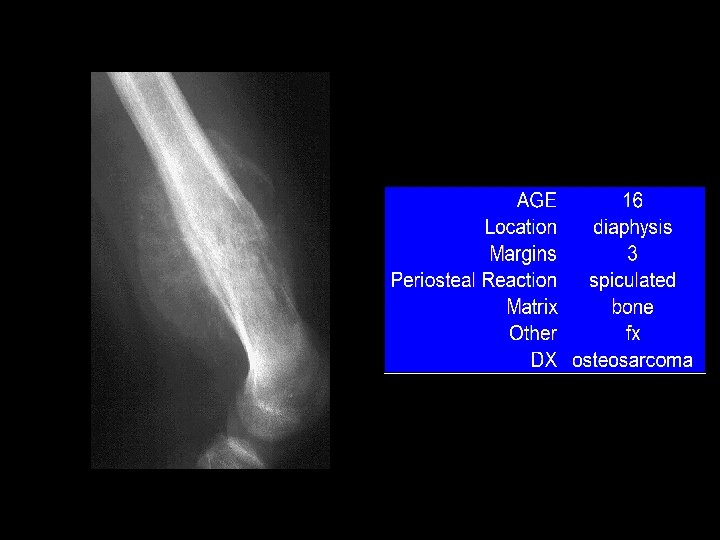

In case of Bone Tumors: look for Location! Age Age Behavior

Location and age of patient most important • parameters in classifying a primary bone tumor. Simple to determine from plain • radiographs.

Reaction of bone to tumor Limited responses of bone • destruction: lysis (lucency) reaction: sclerosis remodeling: periosteal reaction Rate of growth determines bone • response slow progression, sclerosis prevails – rapid progression, destruction prevails –